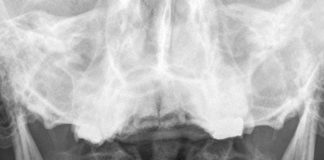

Odontoid kırıkları genellikle yüksek enerjili travmalarla sonucunda oluşmaktadır. Günümüzde oldukça sık görülen servikal travmalar, hayat boyu süren sakatlıklara neden olabileceği için büyük önem taşımaktadır....

Atlas kırıkları çoğunlukla motorlu taşıt kazaları ve düşme sonrası meydana gelmektedir. Atlas kırıklarını ayrıntılı olarak değerlendirmek ve sınıflandırmak için bilgisayarlı tomografi (BT) her zaman...

Servikal omurga baş ile gövde arasında yer alan başın dik durmasını sağlayan, spinal korda ve hayati nöral organlara koruyuculuk yapan bir yapıdır. Çevresinde; nörovasküler...